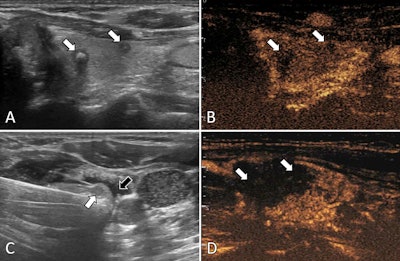

Ultrasound images in a 57-year-old female patient with multifocal papillary thyroid carcinoma. (A) Routine ultrasound scan shows two hypoechoic papillary thyroid carcinoma nodules (arrows) in the left lobe. (B) Preablation contrast-enhanced ultrasound image shows hypoenhancement in the arterial phase (arrows). (C) Isolating fluid (black arrow) is used to protect the muscles beside the nodule (white arrow) during the ablation. (D) Postablation contrast-enhanced ultrasound image shows no enhancement in the original tumor zone (arrows). Image courtesy of the RSNA.